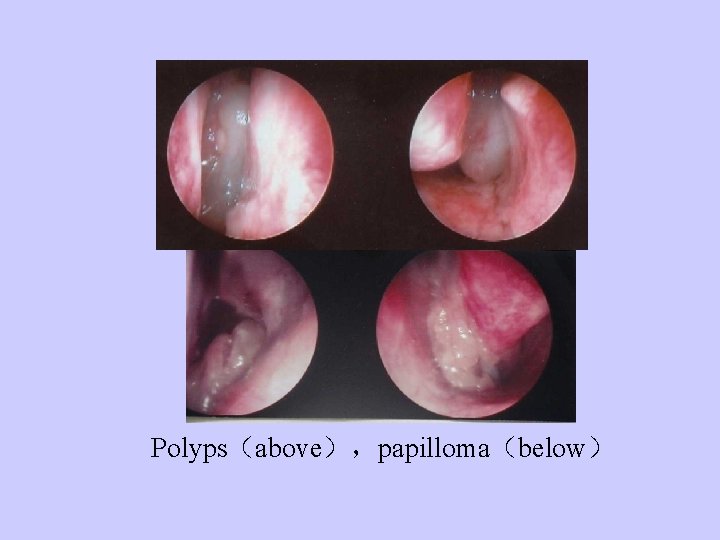

Polyps(above),papilloma(below)